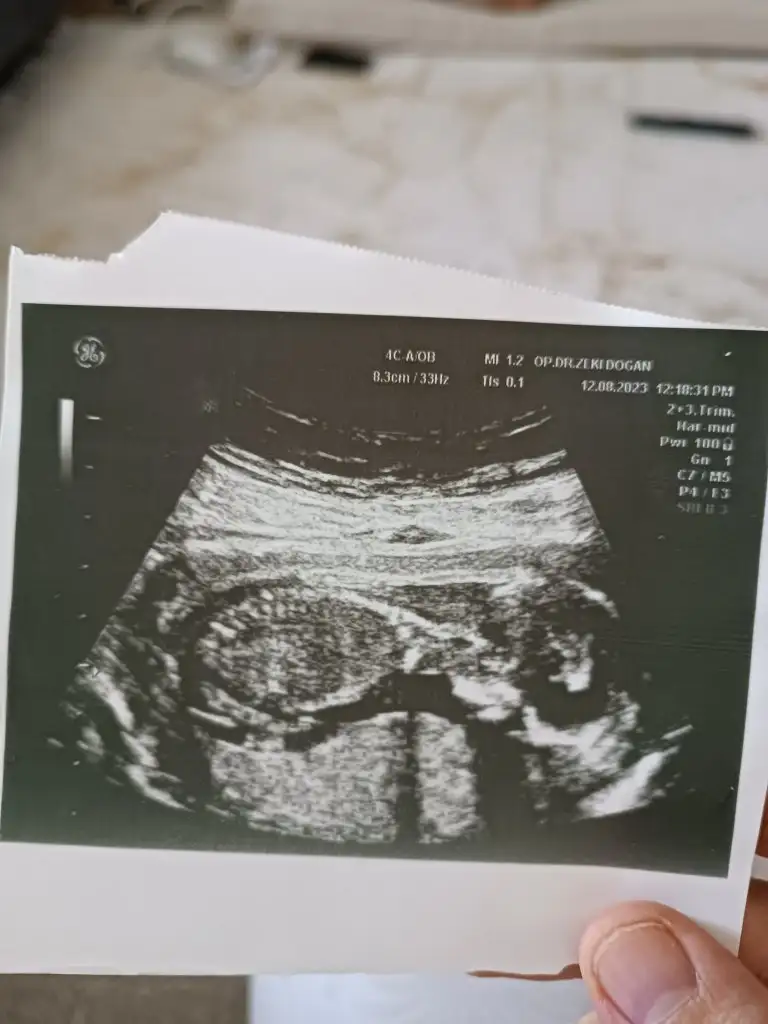

Sizin tahmin ne 15 haftalık fotoğraf buBebeğiniz ters mi duruyor bana mı öyle geliyor

Başka bir ultrason varsa bakabilir miyim kıza benziyor sankiSizin tahmin ne 15 haftalık fotoğraf bu

Biri 8 haftalık iken diğeri ise 14 haftadaBaşka bir ultrason varsa önceki haftalara dair daha net görünen

Kıza benziyor canımBiri 8 haftalık iken diğeri ise 14 haftada